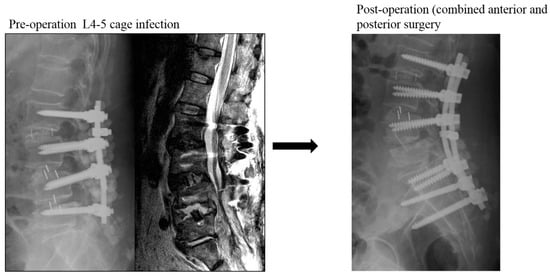

The other 13 patients were grouped into the control group (Figure 2), including 4 women and 9 men with a mean age of 66.6 years at surgery. All patients in this group underwent revision surgeries by simultaneously or staged anterior combining posterior surgery for infectious spondylodiscitis. All infected cages were removed, and reconstructions were performed with autologous iliac tricortical bone grafts or allogenic cortical bone grafts. The mean BMI, CCI, and ASA were 26/8 ± 3.4 kg/m2, 2.0 ± 1.2, and 3.0 ± 0.0, respectively. The average interval between primary and revision surgery was 99.4 ± 84.7 days. The L4-5 segment was still the most common infection site (10/13). The total sum of anterior and posterior revision surgery mean operation time and blood loss were 449.5 ± 91.3 min and 1106.9 ± 536.5 mL, respectively. Eleven patients had positive culture data, and Staphylococcus species (seven cases) remained the most common pathogens. The average hospital stay was 32.6 days, and all patients were doing well by the final follow-up. The mean VAS score was 7.8 ± 0.8 before revision surgery and improved to 3.0 ± 1.1 at the last follow-up. Finally, the ODI also improved from 48.1 ± 8.7 preoperatively to 18.5 ± 14.1. There were three patients with poor healing of posterior wounds, including one patient who needed removal of all posterior instrumentations when the anterior infection segment was fused. The average anterior fusion scale score was 1.4: eight patients with grade I, four patients with grade II, and one patient with grade III.

Figure 2. A case within the control group: L4-5 cage infection treated by anterior removal of cage and fusion, followed by posteriorly removal of L5 and extending instrumentation to S1 and ilium.